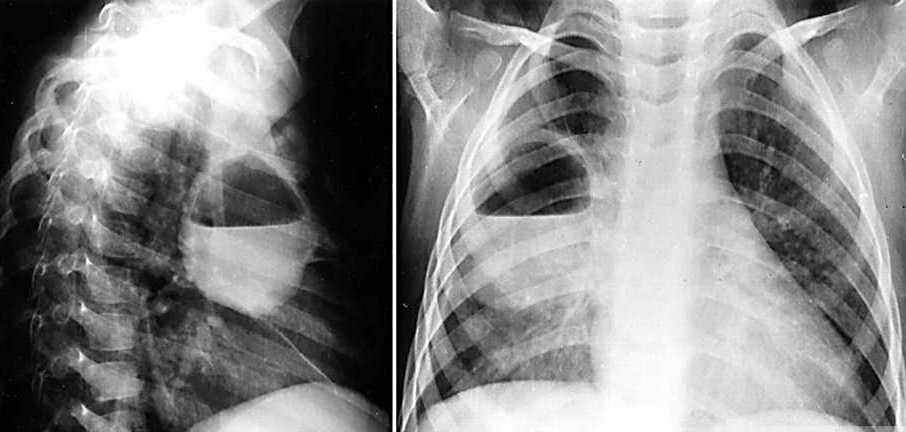

• Рентгенография: рекомендуется рентгенография ОГК в 2-х проекциях, показывающая округлые тени с горизонтальным уровнем жидкости, области инфильтрации или распада, контуры объемных образований. Для уточнения диагноза назначается МСКТ, позволяющая детально визуализировать патологические изменения.

Абсцесс легкого - причина неприятного запаха мокроты.